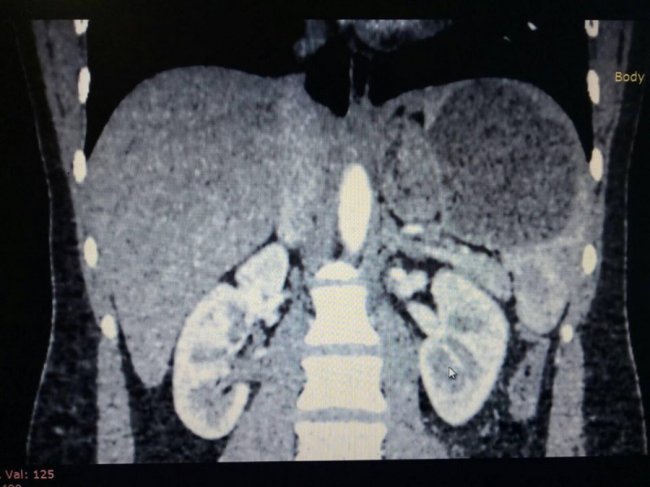

Хірурги відділення ургентної хірургії Луцької міської клінічної лікарні вперше виконали лапароскопічну спленектомію, тобто хірургічне втручання, під час якого селезінку видалили лапароскопічним доступом на закритій черевній порожнині (без розрізу живота).

"Звернулась 21-річна пацієнтка. У неї діагностували кісту селезінки великих розмірів. Це новоутворення загрожувало її здоров’ю", - розповів лікар-хірург Олександр Масіков, який разом з завідувачем відділення ургентної хірургіїАртемом Комарницьким та лікарем-хірургом Святославом Кропивським прооперували хвору.

Селезінку видалили з черевної порожнини через чотири невеликих отвори. Таким чином зробили пацієнтці мінімальну операційну травму. При цьому, за словами лікарів, максимально скорочується термін лікування і реабілітації, а також є хороший косметичний ефект. Тобто, відсутні післяопераційні дефекти у вигляді великих швів, які спостерігаються при операціях з розрізом, стверджує Олександр Масіков.